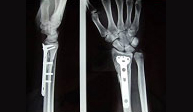

La articulación de la muñeca une las regiones del antebrazo y la mano implicando la porción inferior del cúbito y radio así como los huesos del carpo.Las fracturas del radio distal son las más frecuentes de la extremidad superior. En gente joven se asocian a traumatismos de alta energía como accidentes de tráfico, caídas desde altura o accidentes deportivos. En el anciano lacarencia de hueso a este nivel (osteoporosis) hace de esta región un lugar muy susceptible de fractura con pequeños impactos.

El paciente de edad se beneficia habitualmente del tratamiento conservador con escayola. En el paciente joven el desplazamiento suele ser difícilmente manejable con inmovilización con yeso por lo que es frecuente la realización de una pequeñaintervención para la recuperación anatómica de la muñeca pudiendo reincorporarse a su actividad habitual en el menor tiempo posible y con el menor riesgo de complicaciones.Dentro de la región anatómica de la muñeca se encuentran los huesos del carpo. El hueso escafoides es el que se fractura con más frecuencia tras caídas sobrela mano en extensión. Es por ello una lesión característica en deportes como motociclismo, ciclismo y patín donde se pueden sufrir traumatismos a gran velocidad. El dolor se localiza siguiendo el eje del pulgar pero a nivel de la muñeca y el dolor a la palpación en esta zona (tabaquera anatómica) es extremo. Las fracturas desplazadas se suelen estabilizar quirúrgicamente sin cicatriz,a través de la introducción percutánea de un tornillo intraóseo que permite el inicio de la movilización de la articulación inmediatamente.